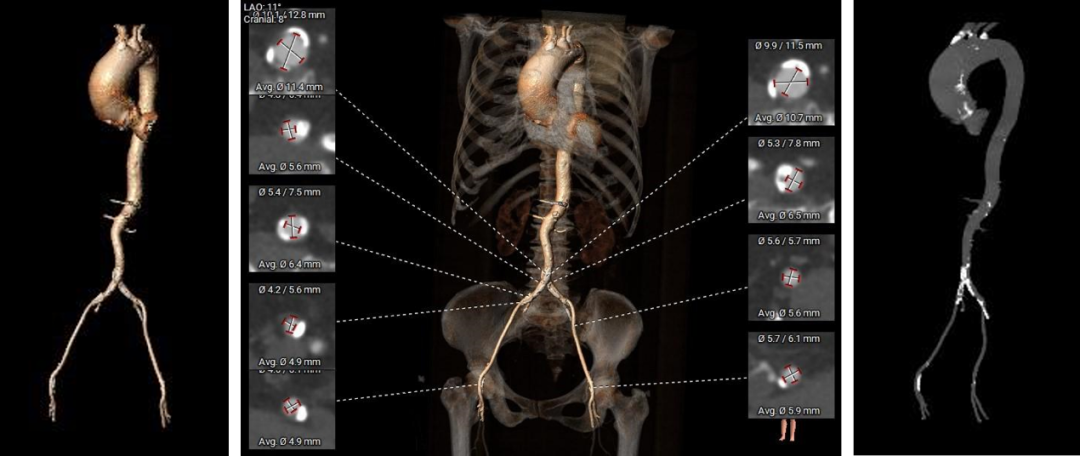

弓部及入路评估

入路血管: 双侧股髂动脉轻度扭曲,髂动脉分叉前后钙化严重,双侧股动脉穿刺位点均有钙化,左侧偏轻;右侧入路血管直径偏细,左侧尚可。